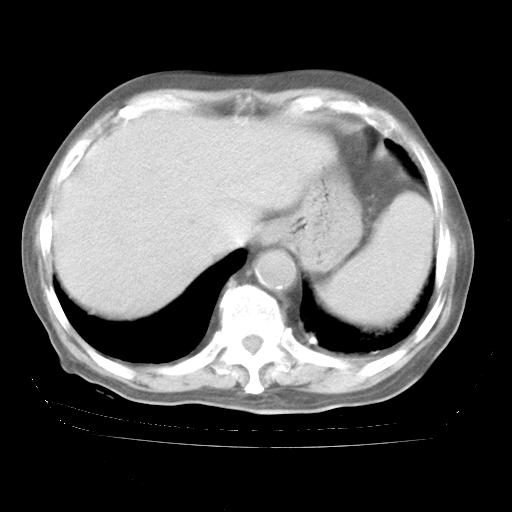

4月28日肺部CT